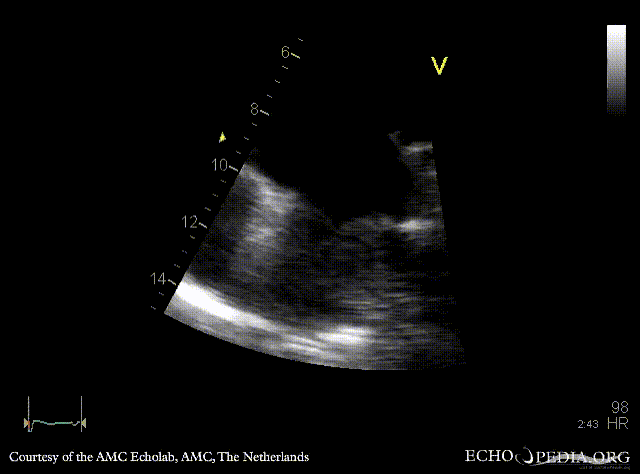

| A4CH, zoom | |